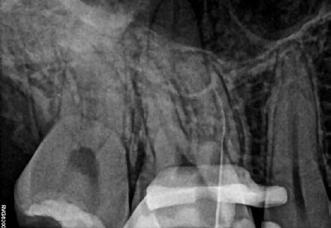

Krell és Caplan kutatásában 2086 repedt fogat vizsgáltak meg. A vizsgált fogak között leggyakrabban a második alsó nagyőrlőfogak (36%), majd ezt követően az első alsó nagyőrlők (27%), és végül az első felső nagyőrlők (18%) fordultak elő. A kutatási eredményeik szerint a fogbél állapota nem befolyásolta jelentős mértékben a kezelés várható kimenetelét. (Irreverzibilis pulpitis 85%; necrosis 80%; korábban gyökérkezelt 74%). A kimenetel szempontjából ugyanígy indifferens volt a páciensek neme, életkora, a kezelés időpontja, a fog pozíciója, a fog helyreállítása során használt anyag típusa, valamint az érintett fogfelszínek száma. 2014 júliusában egy 45 éves hölgy páciens azzal a panasszal kereste fel a rendelőnket, hogy nagyjából 10 napja egy fájdalmas duzzanat alakult ki a jobb felső első kisőrlője koronája mellett (14). A klinikai vizsgálat során egy amalgámtömést találtunk a panaszos fogban. A tömés széli zárása nem volt megfelelő, a disztális záróléc és a tömés között rést tapasztaltunk. A fog disztobukkális és linguális felszíne mellett 8 mm-es csontos tasakokat mértünk. A periapikális felvételen az 14-es foggyökér disztális felszínének megfelelően vertikális irányú radiolucens felritkulást észleltünk. A klinikai vizsgálat során a mesiális zárólécet kettéválasztó törésvonalat detektáltunk (17–18. ábra). A fogszenzibilitás vizsgálata során negatív eredményt kaptunk. A páciensnek ismertettük az elérhető terápiás lehetőségeket: 1, a 14-es fog eltávolítása, majd a foghiány 3 tagú cementezett híddal történő pótlása; 2, a 14-es fog eltávolítása, kemény- és lágyszöveti augmentáció, majd implantátum behelyezése; 3, a 14-es fog gyökérkezelése, gyökértömése és ezt követően a csücsökborítást biztosító restaurátum készítése. Arra is felhívtuk a páciens figyelmét, hogy a 3. terápiás lehetőség választása esetén nem tudjuk a fogmegtartás sikerességét garantálni, de végül – főként anyagi okok miatt – mégis ezt a terápiás opciót választotta. Fontos megjegyezni, hogy a repedt fogak ellátási lehetőségeit a törésvonal mélysége, elhelyezkedése, lefutása nagyban befolyásolja. A kezelés megtervezése során a fog és a fogat körülvevő szövetek állapotával kapcsolatos számtalan különböző faktort kell egyidejűleg figyelembe vennünk. A gyökérkezelést követően a gyökértömést meleg vertikális kondenzációs technikai alkalmazásával készítettük el (19. ábra). A hozzáférési nyílást folyékony és hibrid kompozit tömőanyag segítségével zártuk. A zárás elkészítése során a dr. David Clark által kifejlesztett Bioclear matricarendszert alkalmaztuk. A 6 éves kontroll során készített (2020) röntgenfelvételen a csontos defektus telődése volt megfigyelhető. Ez is a parodontális defektus gyógyulását igazolta (20–21. ábra).

17. ábra: A 14-es fog gyökerének disztális felszíne mellett vertikális csontpusztulásra utaló jelek észlelhetőek. Klinikailag ezen a területen 8 mm mélységű tasakmélységet mértünk. – 18. ábra: A 14-es fog disztális zárólécének megfelelően törésvonal észlelhető, ugyanakkor a csücskök teljes szeparálódására utaló jelek nem láthatóak. Az amalgámtömés eltávolítását követően jól megfigyelhető volt a törésvonal teljes lefutása. – 19. ábra: A gyökértömés elkészítése során meleg vertikális kondenzációs technikát alkalmaztunk. A felvételeken oldalcsatornák jelenlétére utaló jelek is észlelhetőek. – 20–21. ábra: A 2020-ban készült kontrollfelvételeken jól látható a csontos defektus telődése. A radiológiai jelek alapján (jól lekövethető gyökérhártyarés) a parodontális ligamentumok regenerációját is vélelmezzük.